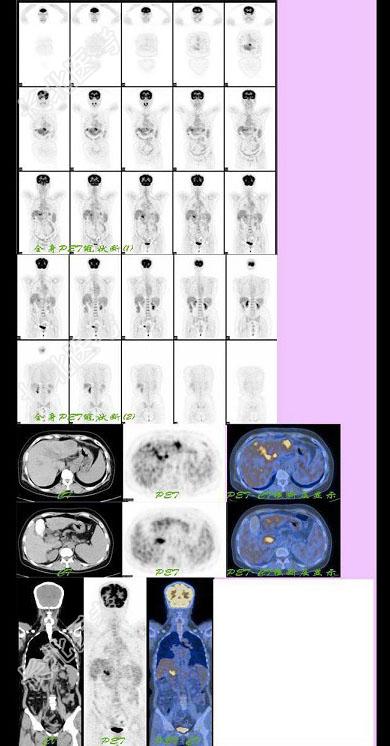

- 单项选择题女,58岁。上消化道出血3个月。B超和CT发现肝硬化、门脉高压, 胃底静脉曲张。B超和CT发现肝左叶占位性病变,可疑肝癌; AFP正常。铁蛋白正常。CEA、CA199、CA125正常。18F-FDG显像最可能诊断为 ( )

A、肠癌肝转移、门静脉癌栓形成

B、肝癌并门静脉癌栓形成

C、肠癌并肝转移

D、肝癌肝内转移

E、以上都不是